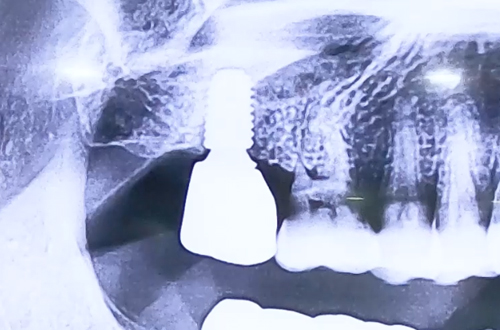

치료 유형 어금니 임플란트 + 상악동거상술

발치한 지 오랜 시간이 지난 오른쪽 위 어금니 임플란트를 진행하신 환자분이십니다.

임플란트 식립이 이루어질 자리와 상악동 사이의 뼈가 얇아

뼈의 두께를 만들기 위하여 상악동거상술과 함께 임플란트를 식립해 드렸습니다.

상악동거상술을 위한 뼈이식 양이 많았기 때문에 단단히 굳기까지 6개월을 기다리신 후

잇몸 부품을 연결해주는 2차 수술을 진행한 뒤 최종 보철까지 마무리하셨습니다.